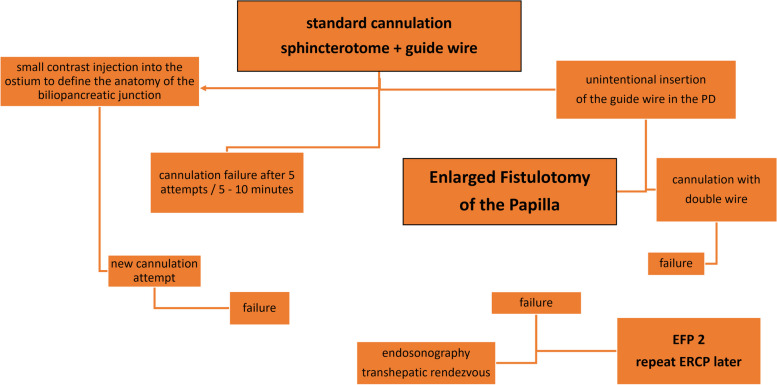

All patients had their exams previously evaluated and underwent preparation with a 12-hour fast before the procedure. Patients who were using antiplatelet agents and anticoagulants were instructed to discontinue these medications. The use of ciprofloxacin 500 mg every 12 hours was indicated for all patients, starting from 6 hours when there was no increase in bilirubin and 24 hours previously in cases of bile duct obstruction in patients with elevated bilirubin levels. All patients were initially submitted to the standard cannulation technique, using the 3-way sphincterotome and 0.035 or 0.025 guide wire, depending on the availability of the brands Olympus®, Boston®, Cook®, MediGlobe®, Scitech® or GFE®. The WEM® electrosurgical generator, model SS200A, was used in all cases. In the case of cannulation failure, following the criteria for indicating early fistulotomy, the patients underwent EFP. After cannulation failure (defined as failing to introduce the guide wire into the bile duct five times, even after injecting a small amount of contrast into the papilla ostium, or the guide wire inadvertently being directed into the pancreatic duct), our preference was to perform EFP early, avoiding trauma to the papilla and the injection too much contrast (Fig. 1).

Our approach to the papilla was always performed first with the sphincterotome and guide wire, avoiding trauma to the papilla and, if necessary, the injection of a small volume of contrast into the ostium to identify the anatomy of the junction of the pancreatic duct and the distal common bile duct. If the guidewire is directed only towards the pancreatic duct, we use the double-wire technique. If we still can’t cannulate the common bile duct, we move on to EFP. The choice between 0.025 or 0.035 wires does not appear to affect the success rate of selective cannulation or the incidence of pancreatitis [ref. 8]. However, the guide wire can cause damage to the pancreatic ducts, especially in multiple cannulation attempts. The guide wire, despite its flexibility, poses a risk of pancreatitis, which can cause intramural dissection, false trajectory and perforation of the main pancreatic duct or its secondary branches. The risk of pancreatitis ranges from 3.5 to 9.7%, and the mortality rate is 0.8% in cases of difficult cannulation [ref. 12, ref. 13].

Difficult cannulation is a subjective term and can be challenging to define. ESGE published a guideline that considers one or more of the following situations difficult cannulation: more than five cannulation attempts; a duration of more than 5 minutes; and more than one cannulation or injection of contrast into the pancreatic duct [ref. 14]. The 2017 International Consensus, on the other hand, defined more than 10 minutes of duration or more than five attempts as difficult [ref. 3]. However, these guidelines are not widely accepted, and in daily practice, these rules are adapted to the different situations of each particular case. According to the results of a previously reported prospective study, the success rate of bile duct intubation in first-time papillary cases is 96% without precutting [ref. 15].